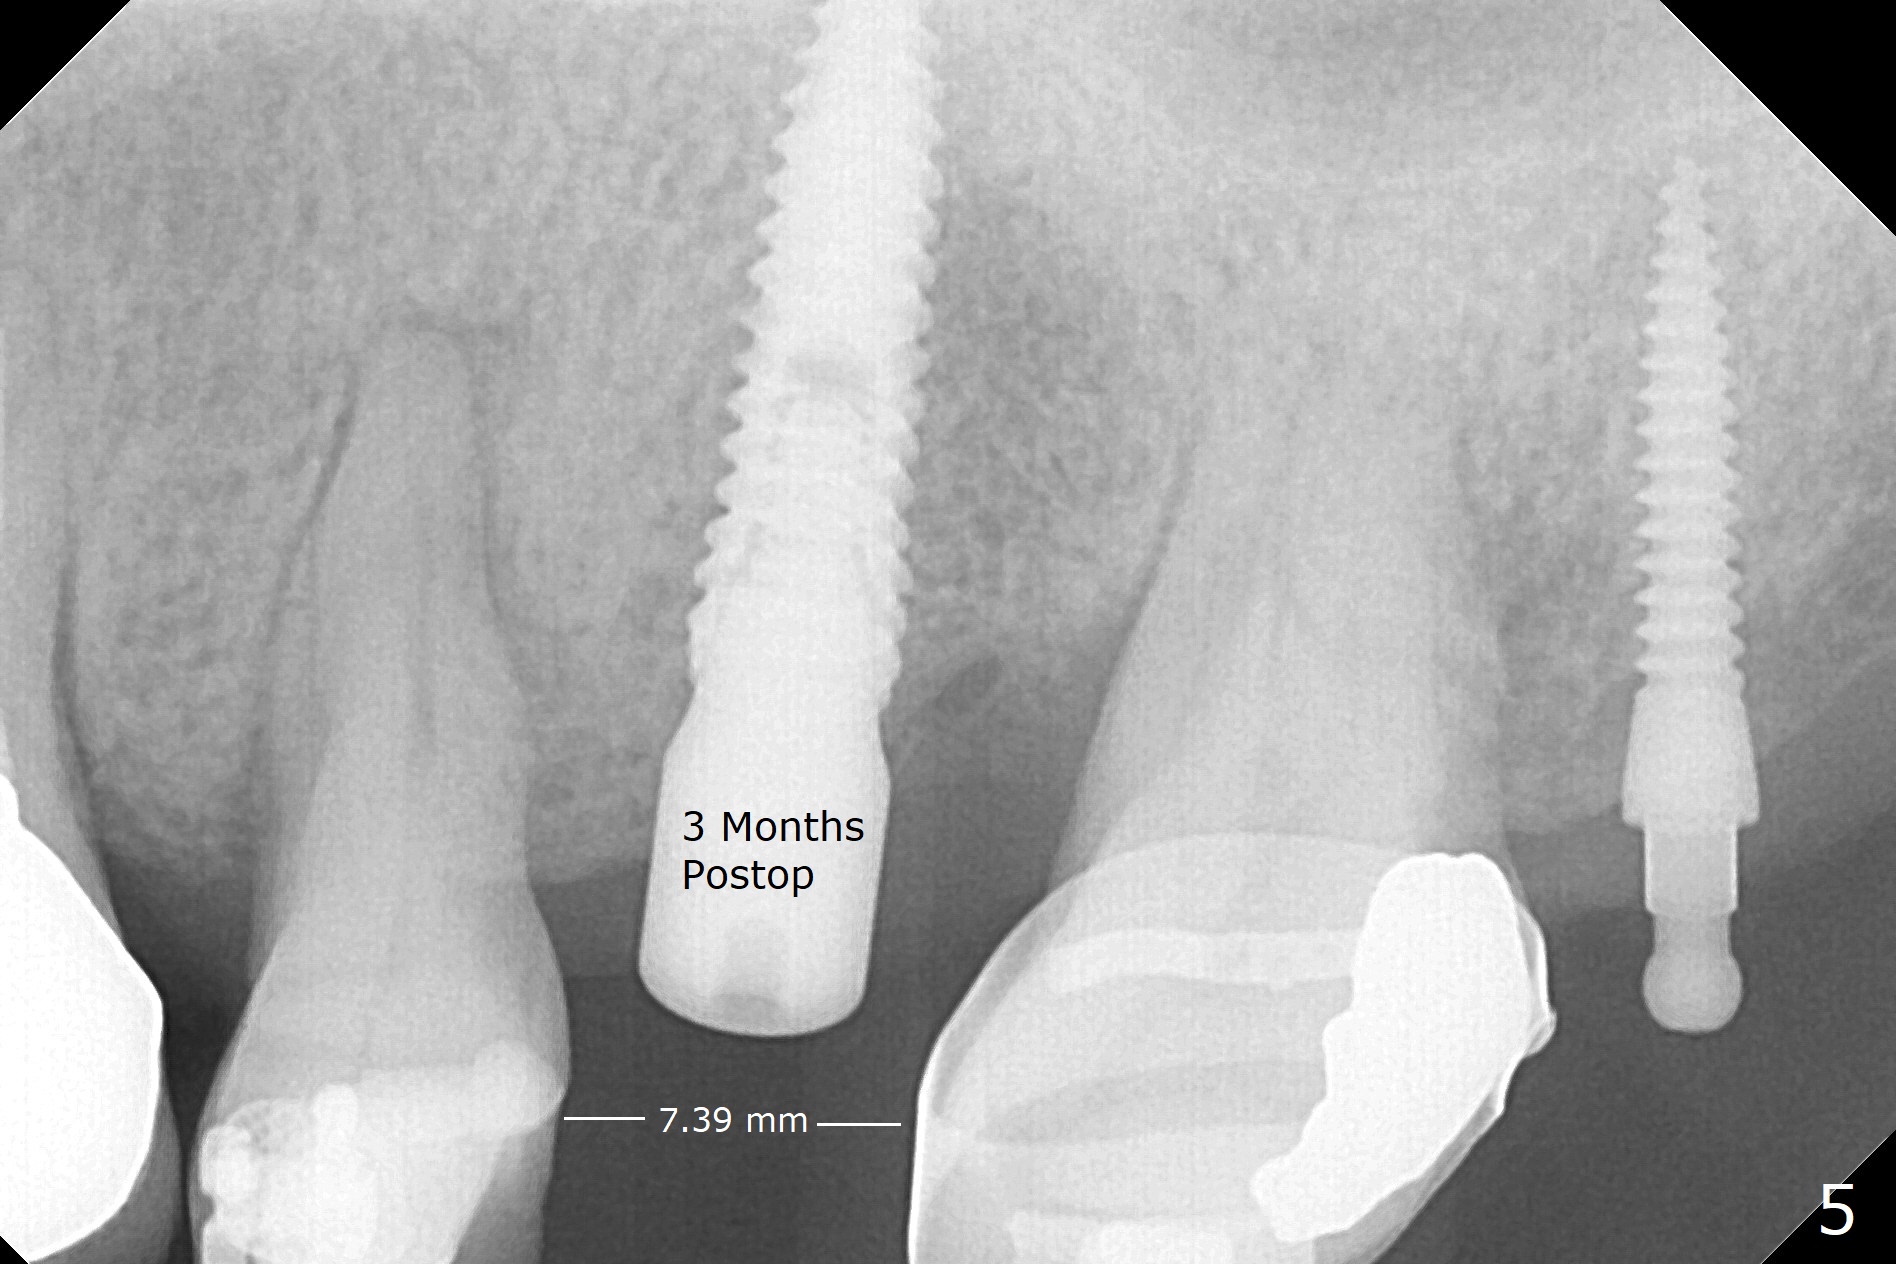

While the implant is being osteointegrated, the edentulous space increases from 5.5 mm to 7.39 mm using the distal anchor implant in 3 months (Fig.5).  The patient is able to masticate normally 1 year 8 months post cementation (Fig.6).  The mesiodistal width of the crown is 7.9 mm.  There is no bone loss 23 months post cementation (Fig.7).